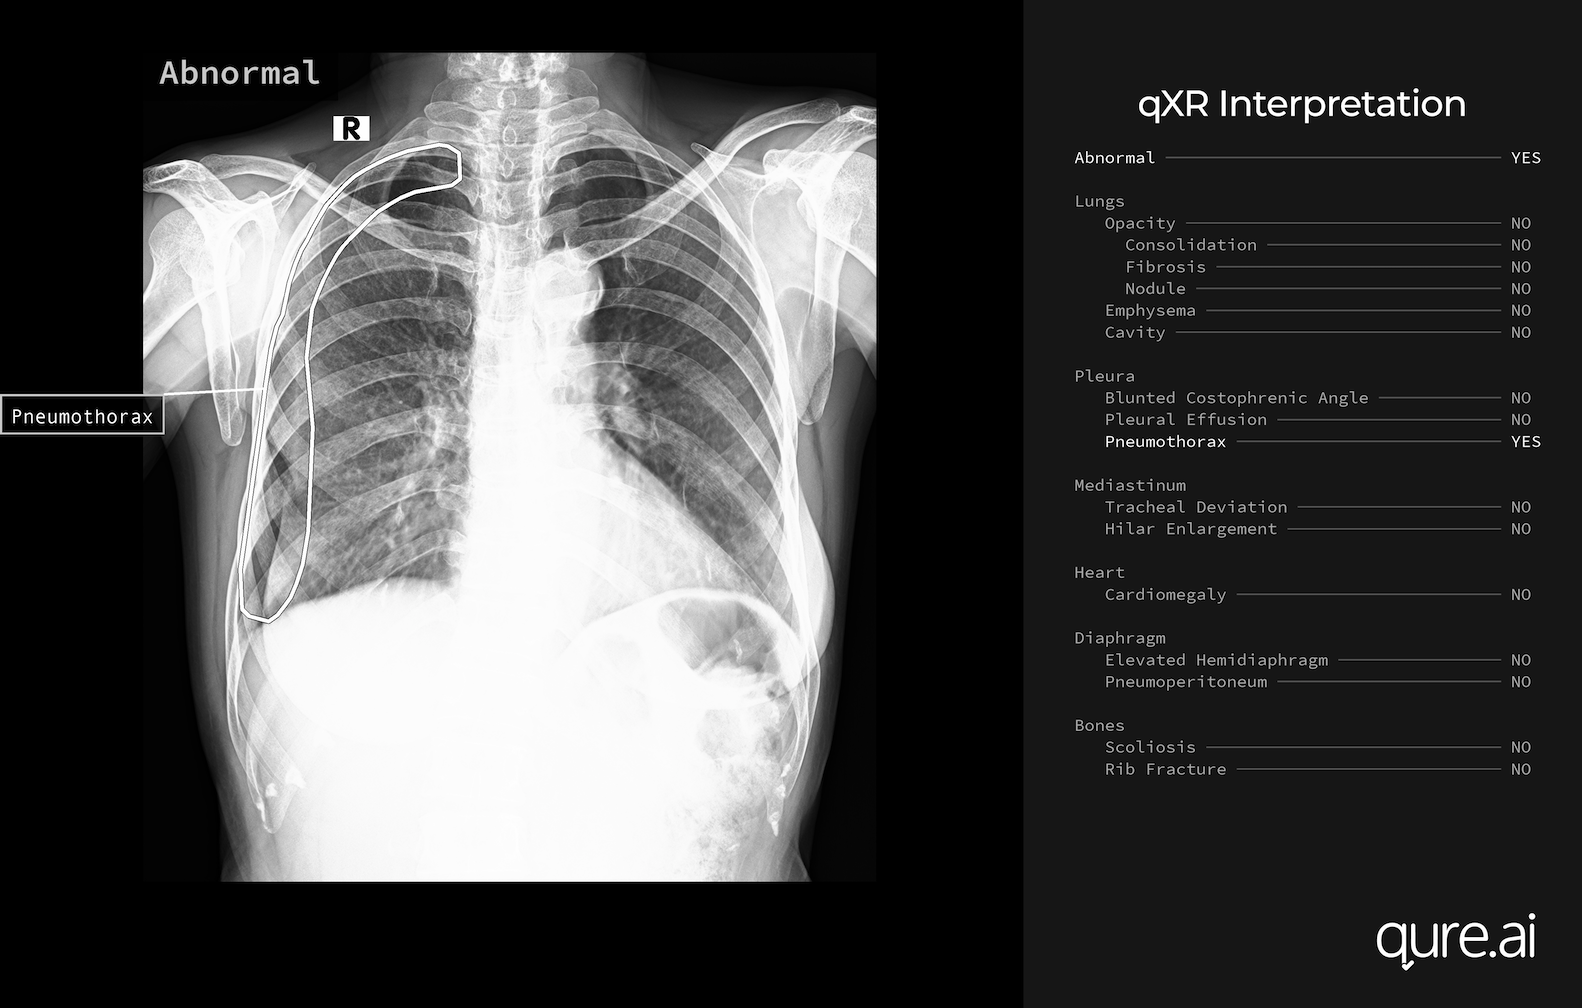

Detection of Pneumonia from Chest X-Ray

Training a classifier on medical images is a crucial task to aid doctors and provide lower cost services to patients. If we can build a classifier that can diagnosis a given disease and provide it to patients who can’t afford a doctor as an app, we have a scalable business. In this project, I have demostrated to perform transfer learning to predict pneumonia in a patient, given their chest x-ray data using Custom Deep Convololutional Neural Network and by retraining pretrained model “InceptionV3” with 5856 images of X-ray